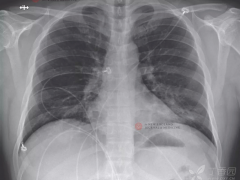

[武汉肺炎]2019新型冠状病毒SARI-> COVID-19

[武汉肺炎]美国首例新冠病毒肺炎的治疗过程

[武汉肺炎]从确诊到康复,一个医学研究生的生死10天